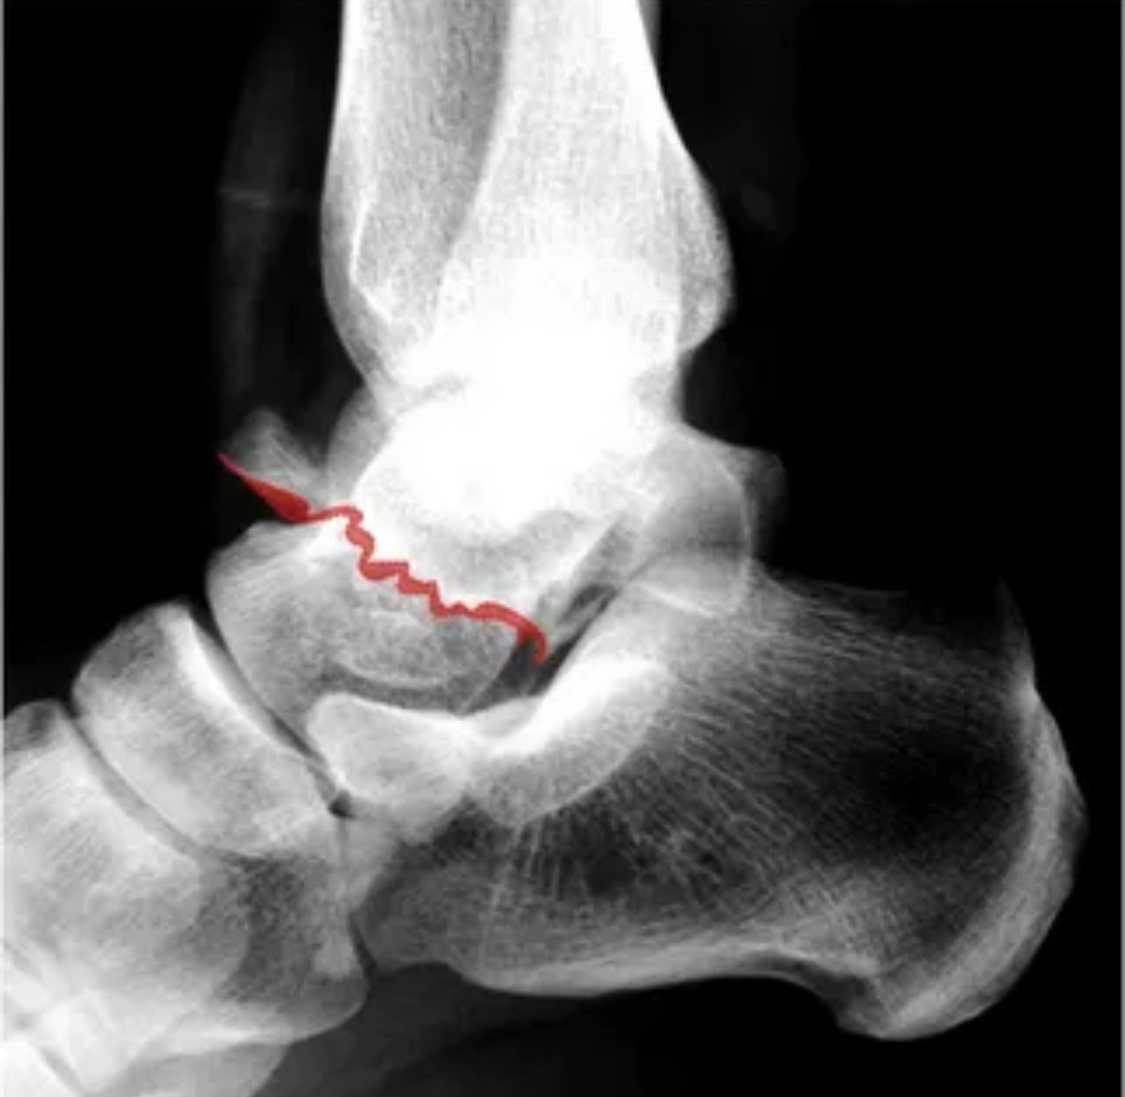

Парень-штурмовик, ехал на бронетранспортёре, наехали на мину. Подбросило в воздух, без сознания приземлился, судя по всему, на ноги. С одной стороны перелом лодыжек, с другой - перелом таранной кости. Эта кость - самая плохо кровоснабжаемая кость тела. Хуже головки бедра. Лечили в гипсе, осколки не вправили, исходно перелом был таким:

-2

но сейчас всё вот так:

-3

То есть отломанная головка таранной кости полностью ушла вверх. Там и лежит уже больше года. За это время парню каких только операций не предлагали, в итоге он потерялся, и не понимает, что же делать дальше. Пришел ко мне за последним мнением (начитался обо мне где-то).